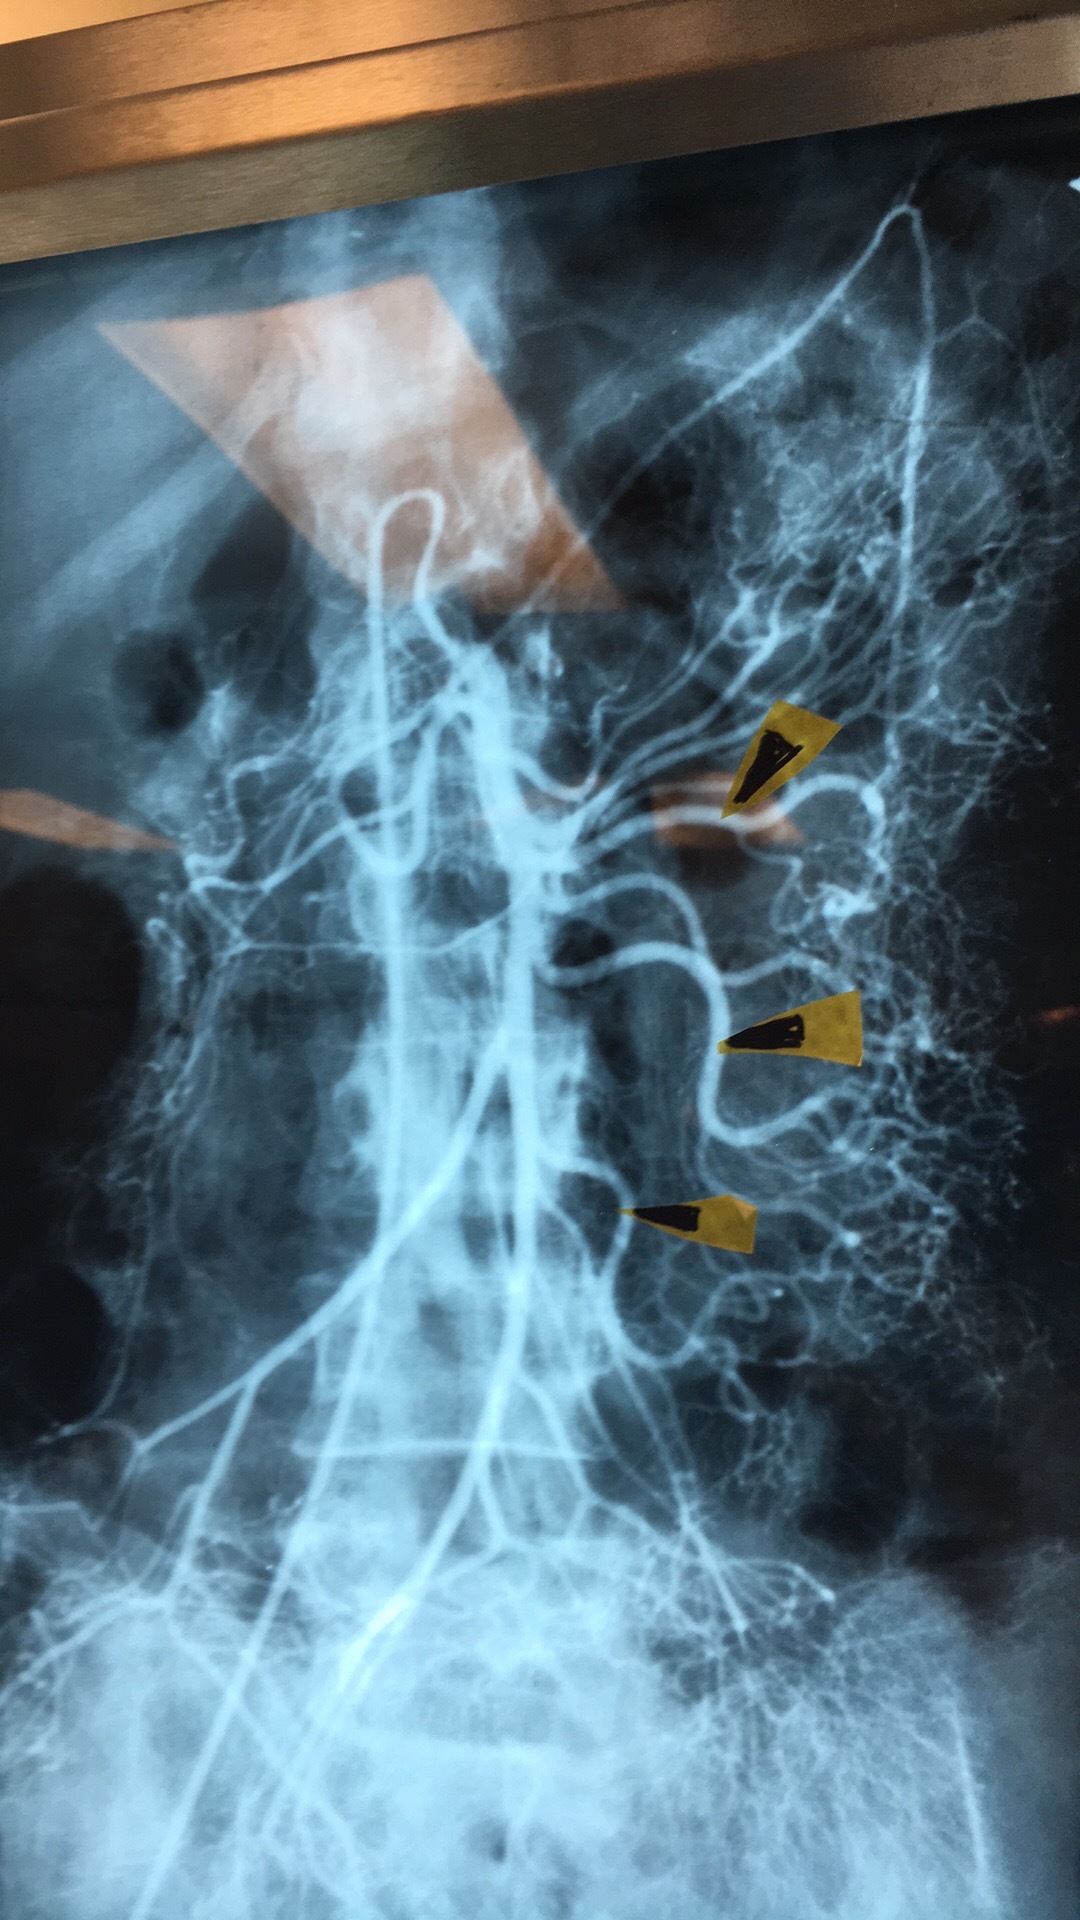

What are these “branches”? From where and what supply?

Intestinal branches. From SMA to Small Intestine (jejunum/ileum).